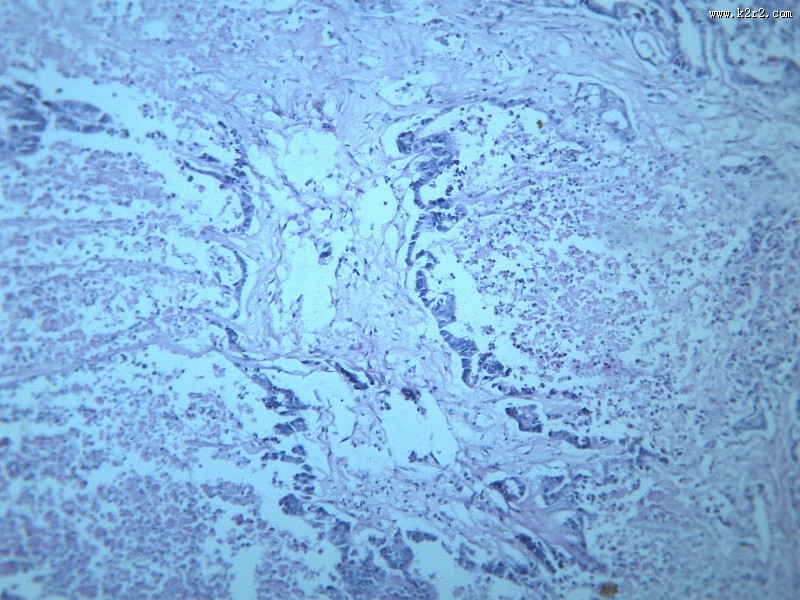

腺癌肝转移大全 - 第8张

腺癌肝转移大全

图集中 / 共有 12 张图片

淋巴结内转移癌

腺癌

医学

显微切片

癌症

腺癌肝转移